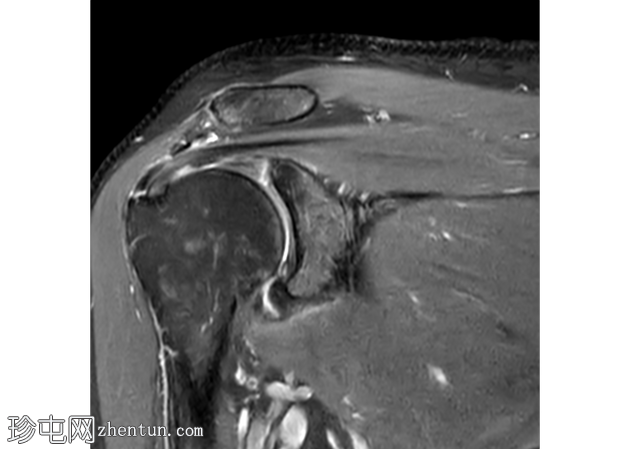

冠状面 T2

脂肪饱和度

冈上肌腱滑囊侧存在部分厚度撕裂,肌腱物质内分层延伸约2厘米,与滑囊侧分层部分厚度撕裂相符。伴有间质性肩胛下肌腱(SST)撕裂。冈上肌体积轻度减少。

肩袖分层撕裂通常被描述为肌腱物质的水平分裂。

其特征性表现是充满液体的裂隙,将关节面和滑囊肌腱层分开,形成“双层”外观。

关节面保持大致连续,而滑囊面不连续且回缩。分层会严重损害肌腱的生物力学。

这通常与外在撞击、骨刺和重复性过顶运动(例如投掷运动员、画家、游泳运动员)有关。